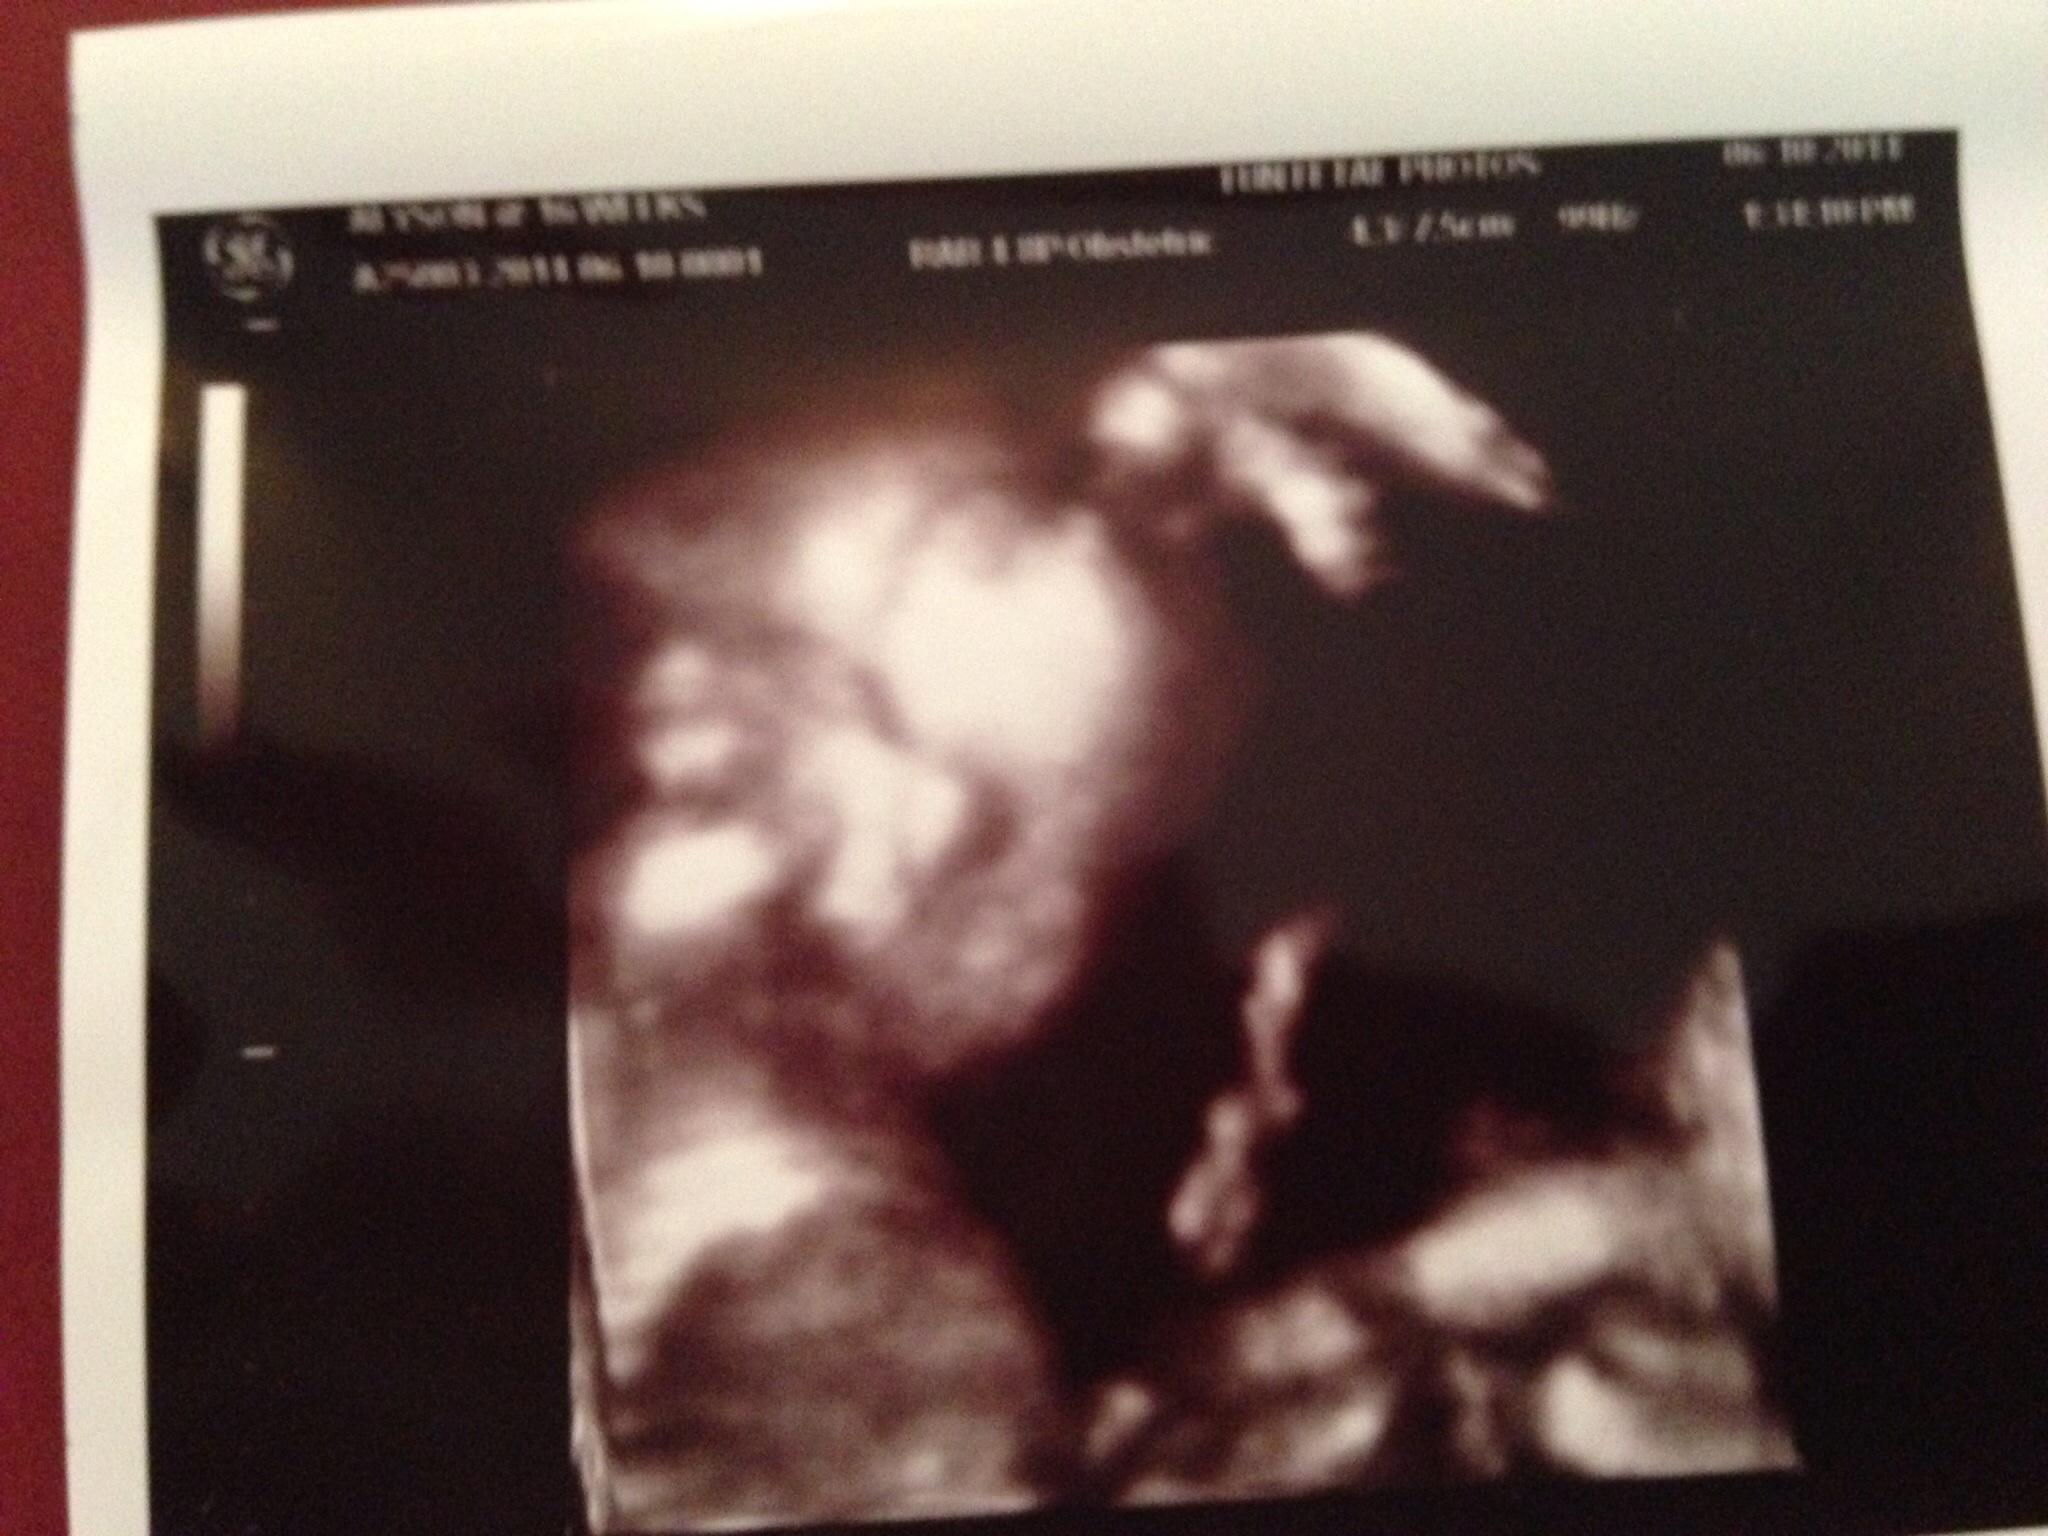

• I did it at 18 weeks and I though it was awesome! My friend did one after 30 weeks and she said it looked exactly like her daughter did as a new born! So I'm going back:) here is a picture of my precious boy last week!

Baby "H" due November 7